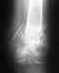

Вот я и сходил к травматологу в поликлинику. Радует, что хоть снимки теперь на руках, можно выложить, что собственно я и сделал. Снимал фотиком, так что если что не разобрать - постараюсь лучше сделать. Скажите, какие дальнейшие действия по нагрузке ноги? А то информации практически нет. Врач принимал другой, не тот что карту мою составлял. Этот только сделал снимок и записал на дальнейший прием в первому врачу. Врач, который проводил операцию, сейчас в отпуске. В больнице травматологи сказали, что можно давать нагрузку, разрабатывать ногу, но потихоньку, и очень аккуратно, а то колено после 2-х месяцев слабое. Оно в действительности, так и есть. Но на двух ногах я уже после 7 недели стоял. только ходил на одной ноге с костылями. Щас пытаюсь ходить с одним костылем, который просто в руке держится. Колено хоть и держит при опоре на костыль, но не долго. Где-то 1-2 секунды. Потом начинает слабеть и болеть. В принципе, чтобы сделать шаг, хватает. Но вот подняться на ступеньку (они пока еще есть в совдеповских квартирах) это сложно. Поэтому в другой руке ношу обычный деревянный костыль.

Отсюда вопрос... Какая нагрузка на ногу возможна при таком состоянии, как на снимках? Колено ведь у человека способно держать очень большую нагрузку. но ведь есть же какие-то ограничения в связи с переломом? После того, как восстановится колено, можно ли будет ходить без костылей, просто хромая на одну ногу? Или до полного сращения не стоит?